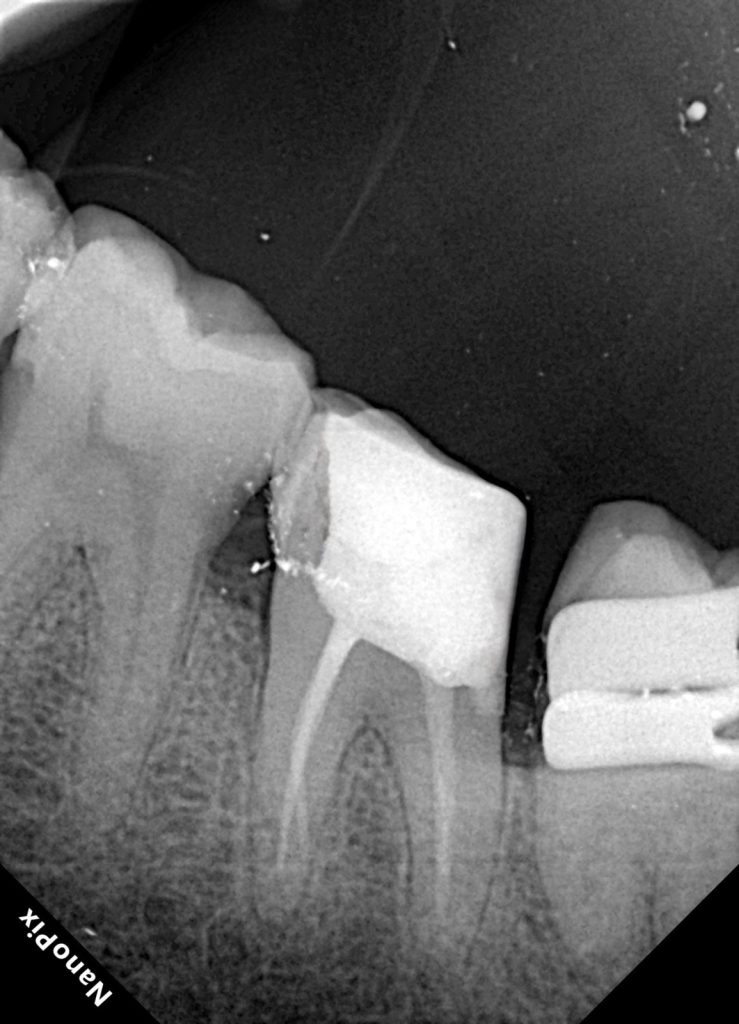

4. Endodontic Therapy Under Magnification

A conservative access was refined to maintain internal strength while allowing complete visualization.

Endodontic protocol included:

d. Obturation

The canals were filled using warm vertical compaction with bioceramic sealer, ensuring three-dimensional obturation and apical seal.

Radiographic results confirmed proper taper, length, and absence of voids.